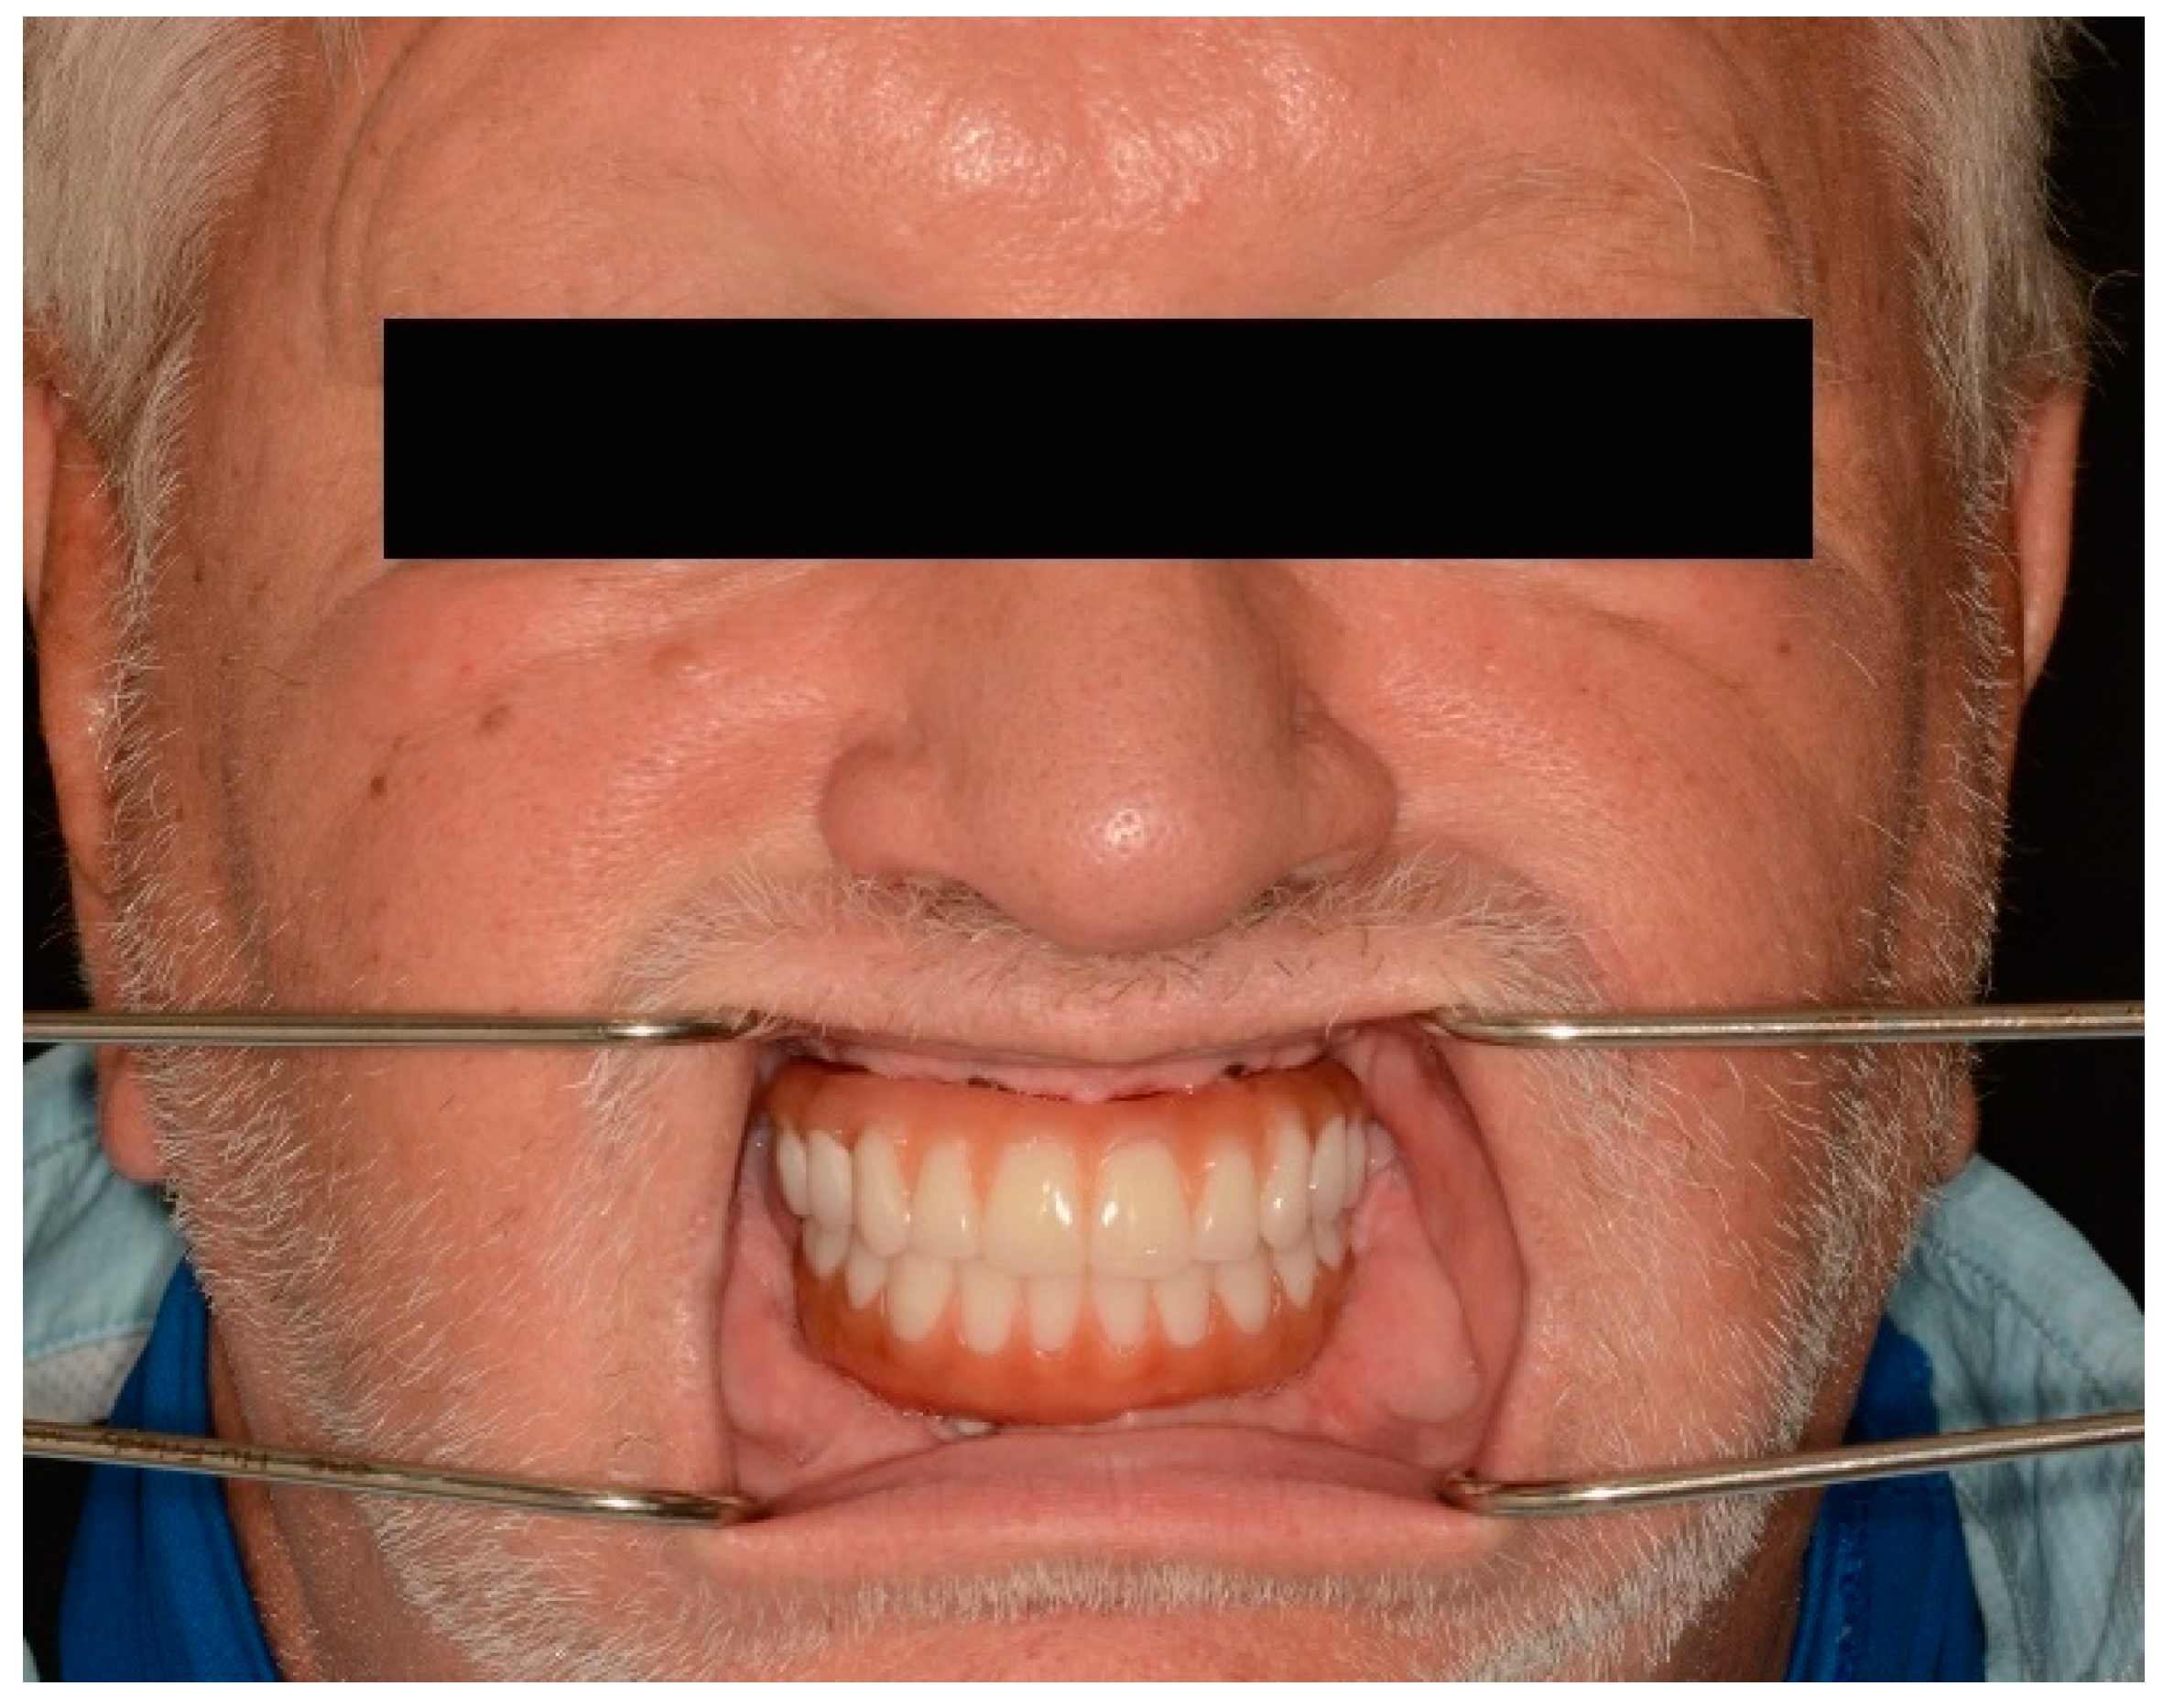

The passivity and accuracy of the fit were assessed clinically and radiographically (Figure 10), and the abutment screws were tightened to the recommended manufacturer’s recommended torque values.

Figure 10.

Panoramic radiograph of maxillary and mandibular prostheses taken at the time of delivery.

Vertical dimension, centric occlusion, protrusive, and laterotrusive excursive movements were assessed and refined (Figure 11). Additionally, cleanability, esthetics, and comfort were deemed adequate by the patient (Figure 11).

Figure 11.

Intraoral photograph of maxillary and mandibular definitive complete-arch implant-supported prostheses. (Top) Centric occlusion. (Bottom) Lateral and protrusive excursions.